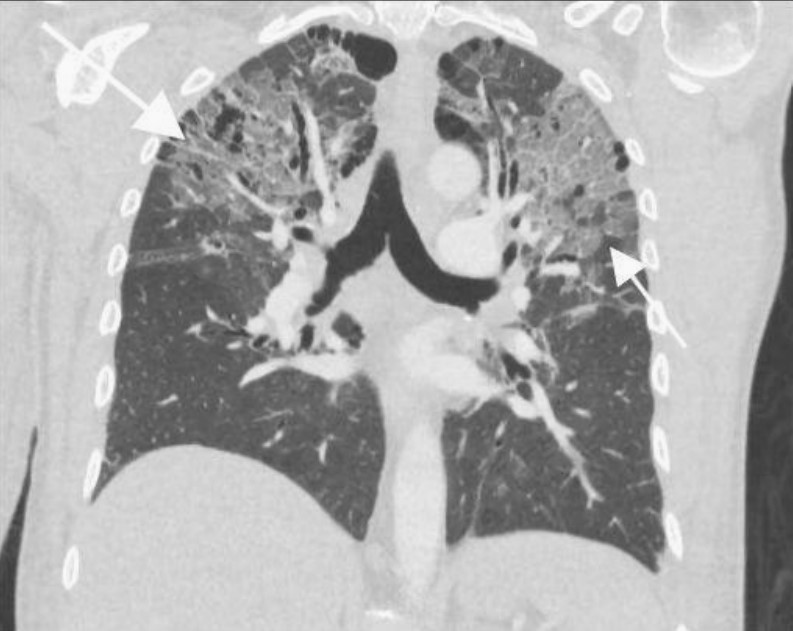

患者左下肢X線片顯示腓骨和脛骨骨折。胸片顯示上肺葉雙側(cè)肺泡混濁,這些不明確的斑片狀氣腔模糊是非特異性的,可見于肺水腫、誤吸或感染。繼續(xù)為患者行胸部CT檢查,CT顯示肺動(dòng)脈干、左或右肺動(dòng)脈主干或肺葉動(dòng)脈無充盈缺損,雙側(cè)胸腔積液。肺窗顯示雙側(cè)上、左中肺野斑片狀磨玻璃影伴小葉間隔增厚。

鑒于患者的骨折和呼吸困難,考慮肺脂肪栓塞。與肺脂肪栓塞相關(guān)的最常見CT結(jié)果包括局灶性或彌漫性磨玻璃影、片狀或彌漫性實(shí)變區(qū)以及各種小結(jié)節(jié)(<10 mm)。罕見觀察到肺動(dòng)脈內(nèi)脂肪衰減充盈缺損。患者最終診斷為肺脂肪栓塞。

圖2 冠狀位CT顯示位于雙上肺野和左中肺野的斑片狀磨玻璃影伴小葉間隔增厚(白色箭頭)